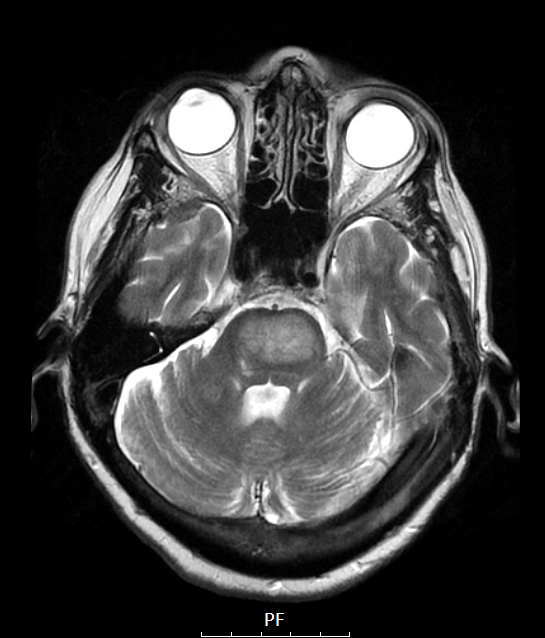

14A2 Lymphoma, Pons (Case 14) T2 NoC

A T2-weighted image identifies the pontine mass as the only hyperintense lesion in this brain.